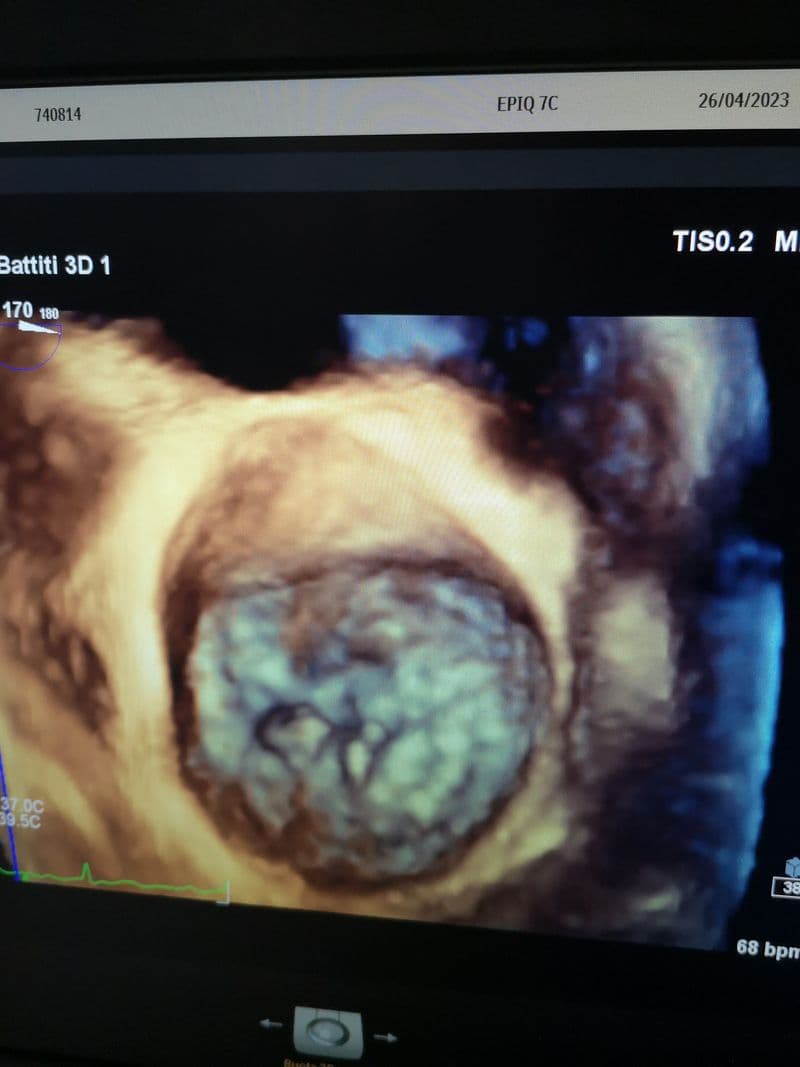

Sono importanti per la cura e trattamento delle malattie cardiovascolari. La possibilità di ottenere immagini a elevata risoluzione con ricostruzione tridimensionale consente, infatti, di inquadrare la patologia valvolare e di definirne la corretta indicazione chirurgica nell’ottica della riparazione e non della sostituzione delle valvole cardiache. L'ecocardiografia tridimensionale consente, inoltre, l'inquadramento della patologia strutturale (per esempio della valvola mitralica, della valvola aortica, del setto interatriale) e il monitoraggio delle procedure interventistiche mininvasive. I nuovi ecocardiografi dispongono anche di un software che permette una diagnosi precoce in caso di sospetta cardiotossicità da chemioterapici e/o da radioterapia.